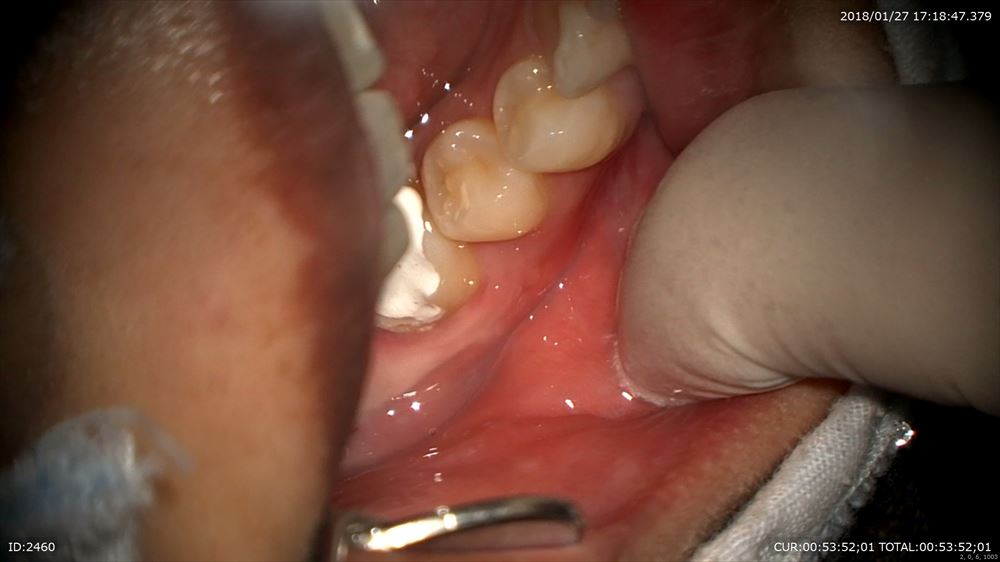

この方は精密根管治療でこの右下の腫れが

今日まで3回根管綺麗になりました。

根管充填

腫れもなくなり。本当に笑顔が戻りましたね!!